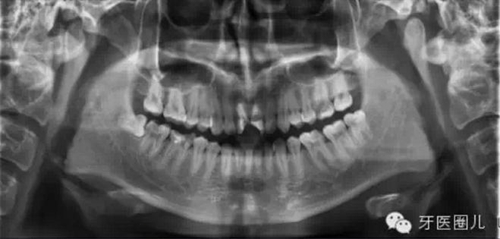

觀察術(shù)前X光片,設(shè)想達(dá)到一個(gè)理想的結(jié)果,然后用這一設(shè)想來指導(dǎo)每一治療步驟,這樣自然會(huì)提高我們的根管治療的操作水平。

患者外傷11 21簡單冠折,選擇一次法完成冷牙膠充填3天后行樁修復(fù)。